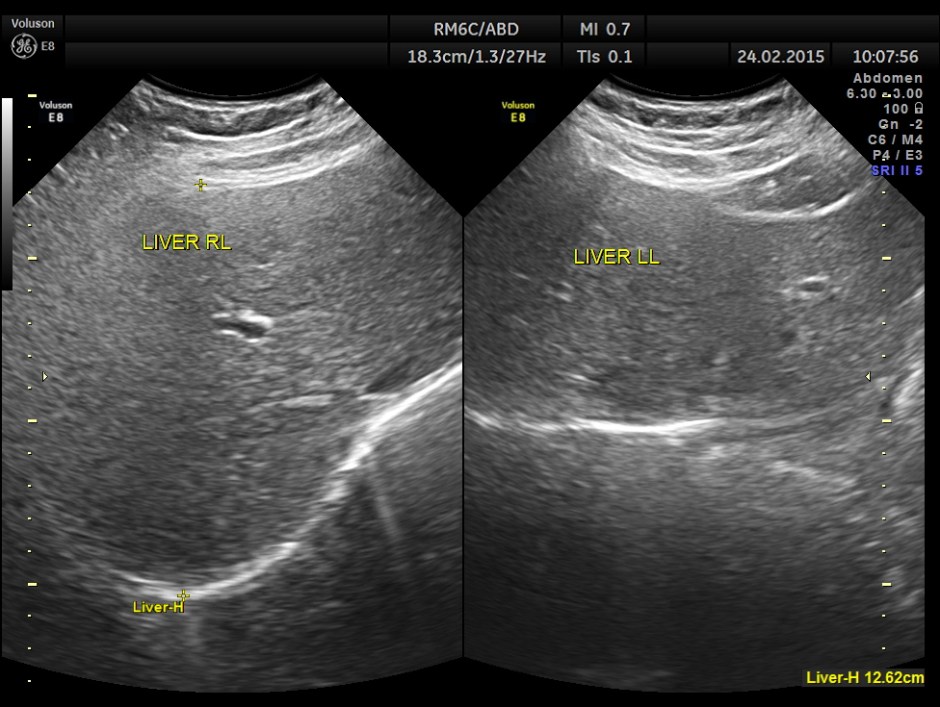

This was a 23 year old young lady , who was evaluated elsewhere for menstrual irregularities . She was reported to have a gallstone . She had no digestive complaints. She went for a 2nd and 3rd opinions, where the gallstone was not seen.She also underwent a CT scan , which reported a shrunk gall bladder and gallstone was not seen. She came to me for another opinion. She was in an over night fasting status ( almost 14 hours after her last meal or drink ).

The following is what was seen.